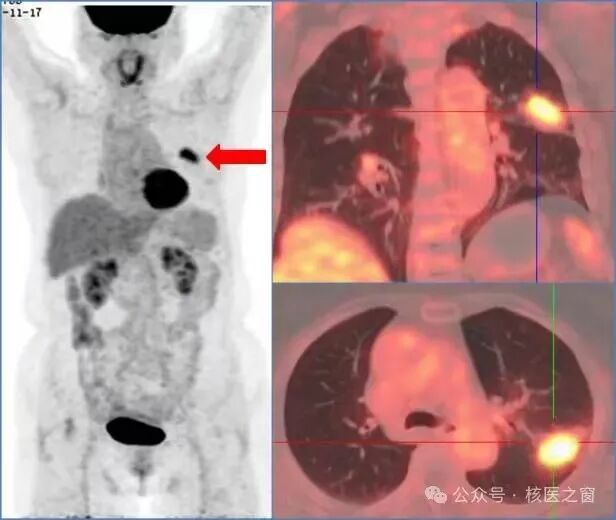

2、明确肿瘤侵犯程度,协助医生为您选择合适的治疗方案

图片